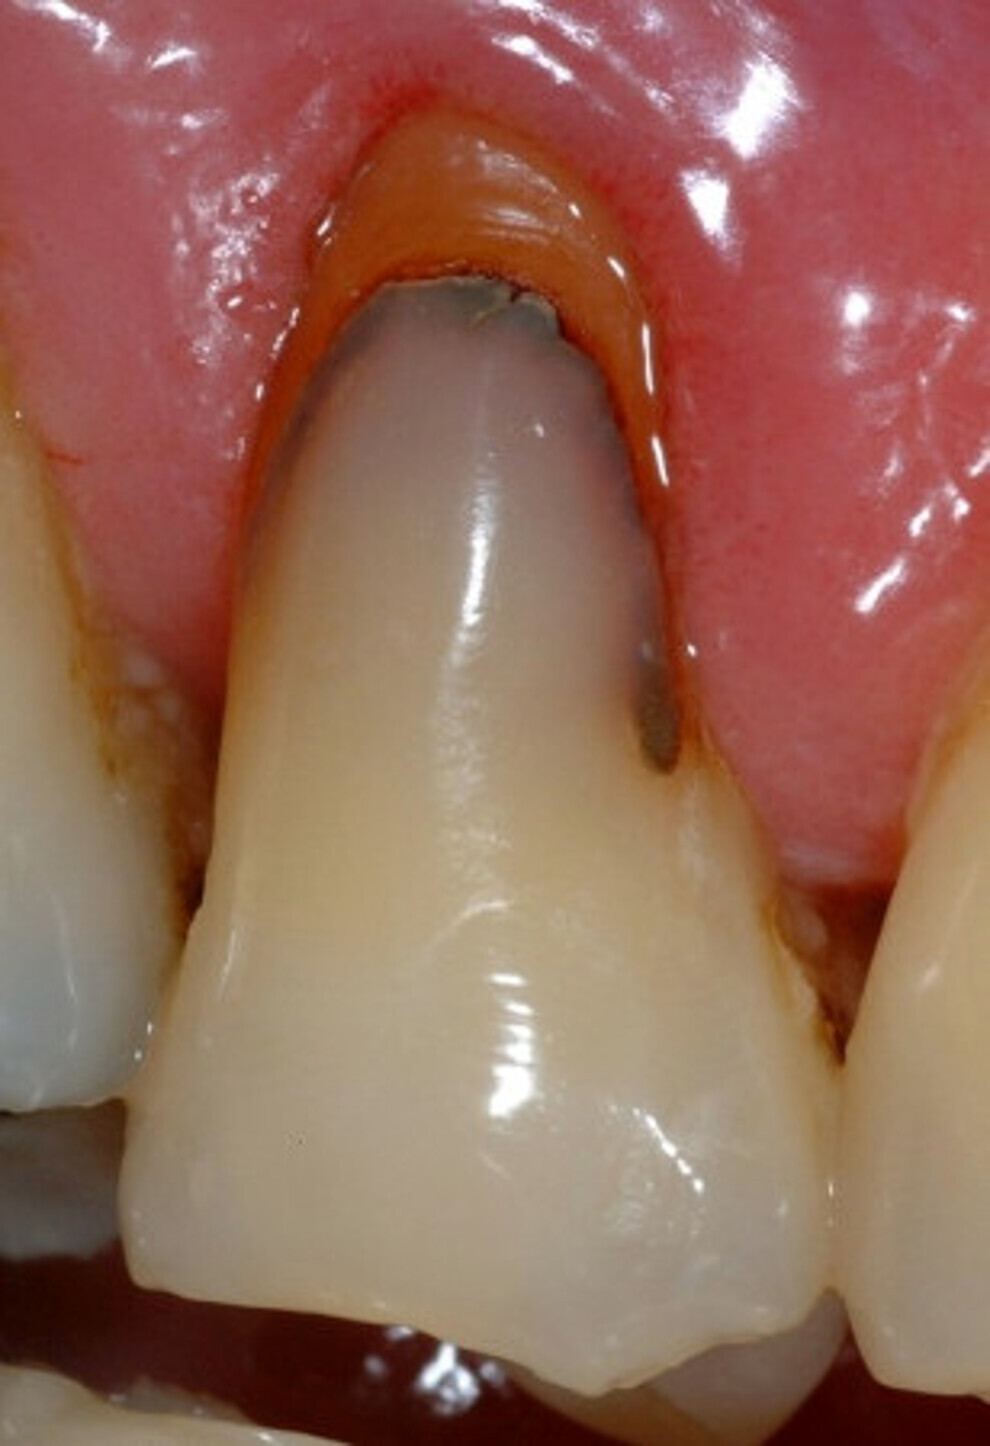

Lésion cervicale non carieuse, avant traitement. Dans les études cliniques randomisées et contrôlées, les verres hybrides montrent des résultats prometteurs pour la restauration des lésions cervicales. (Photo : Prof Falk Schwendicke)

En ce qui concerne les verres hybrides, les seules données disponibles sont des études randomisées qui ont comparé ce matériau avec les résines composites dans les lésions non carieuses (Fig. 4).

Fig. 4a : Dans les études cliniques randomisées et contrôlées, les verres hybrides montrent des résultats prometteurs pour la restauration des lésions cervicales. a) Lésion cervicale non carieuse, avant traitement,